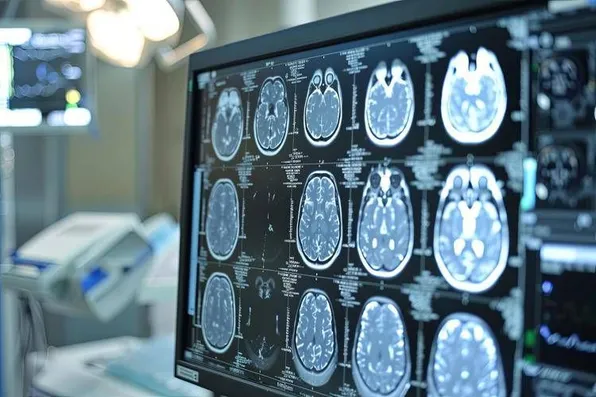

Le apparecchiature, “per ogni spoke e hub, si compongono di una stazione robotizzata con un monitor, telecamera e altoparlante per vedere il paziente in televisita o teleconsulto - spiega Biondina - Negli spoke, a differenza degli hub, ci sono anche i dispositivi per la valutazione dei parametri vitali. Le dotazioni dialogano con le strutture aziendali. Per i pazienti con sospetto ictus ischemico che arrivano in pronto soccorso (Ps) di centri spoke, dove non c’è la neurologia, il medico di Ps può chiedere la televisita o condividere esami di imaging diagnostico con il centro hub. Gli spoke di Asl Salerno - precisa l’ingegnere - permettono ai pazienti di effettuare tac e angiotac con o senza mezzo di contrasto visibili al neurologo a decine di chilometri di distanza”.

Come è noto la tempestività della diagnosi e della terapia “riducono i danni da ictus - sottolinea l’esperta - per questo la rapida presa in carico del paziente fa la differenza: attivando, da parte del medico di ps il contatto con il neurologo da remoto, nel giro di circa 40 minuti permette di gestire il paziente attivando la trombolisi endovenosa ed evitare la trobectomia meccanica, procedura più invasiva, che comporta anche il trasferimento ad altra struttura. Nel giro di un anno - tra febbraio 2024 e marzo 2025 - ci sono state 261 connessioni - conclude - L’obiettivo è di ampliare l’impiego di questo modello anche per la rete cardiologica”.